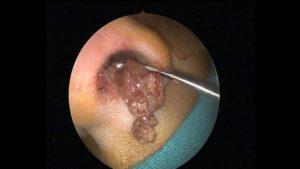

Необычное длительное тропическое заболевание, проявляющееся воспалительным процессом слизистой оболочки носоглотки и образованием папилломатозных опухолей.

При риноспоридиозе образования на слизистой напоминают форму «ягод малины» или «кочанов капусты».